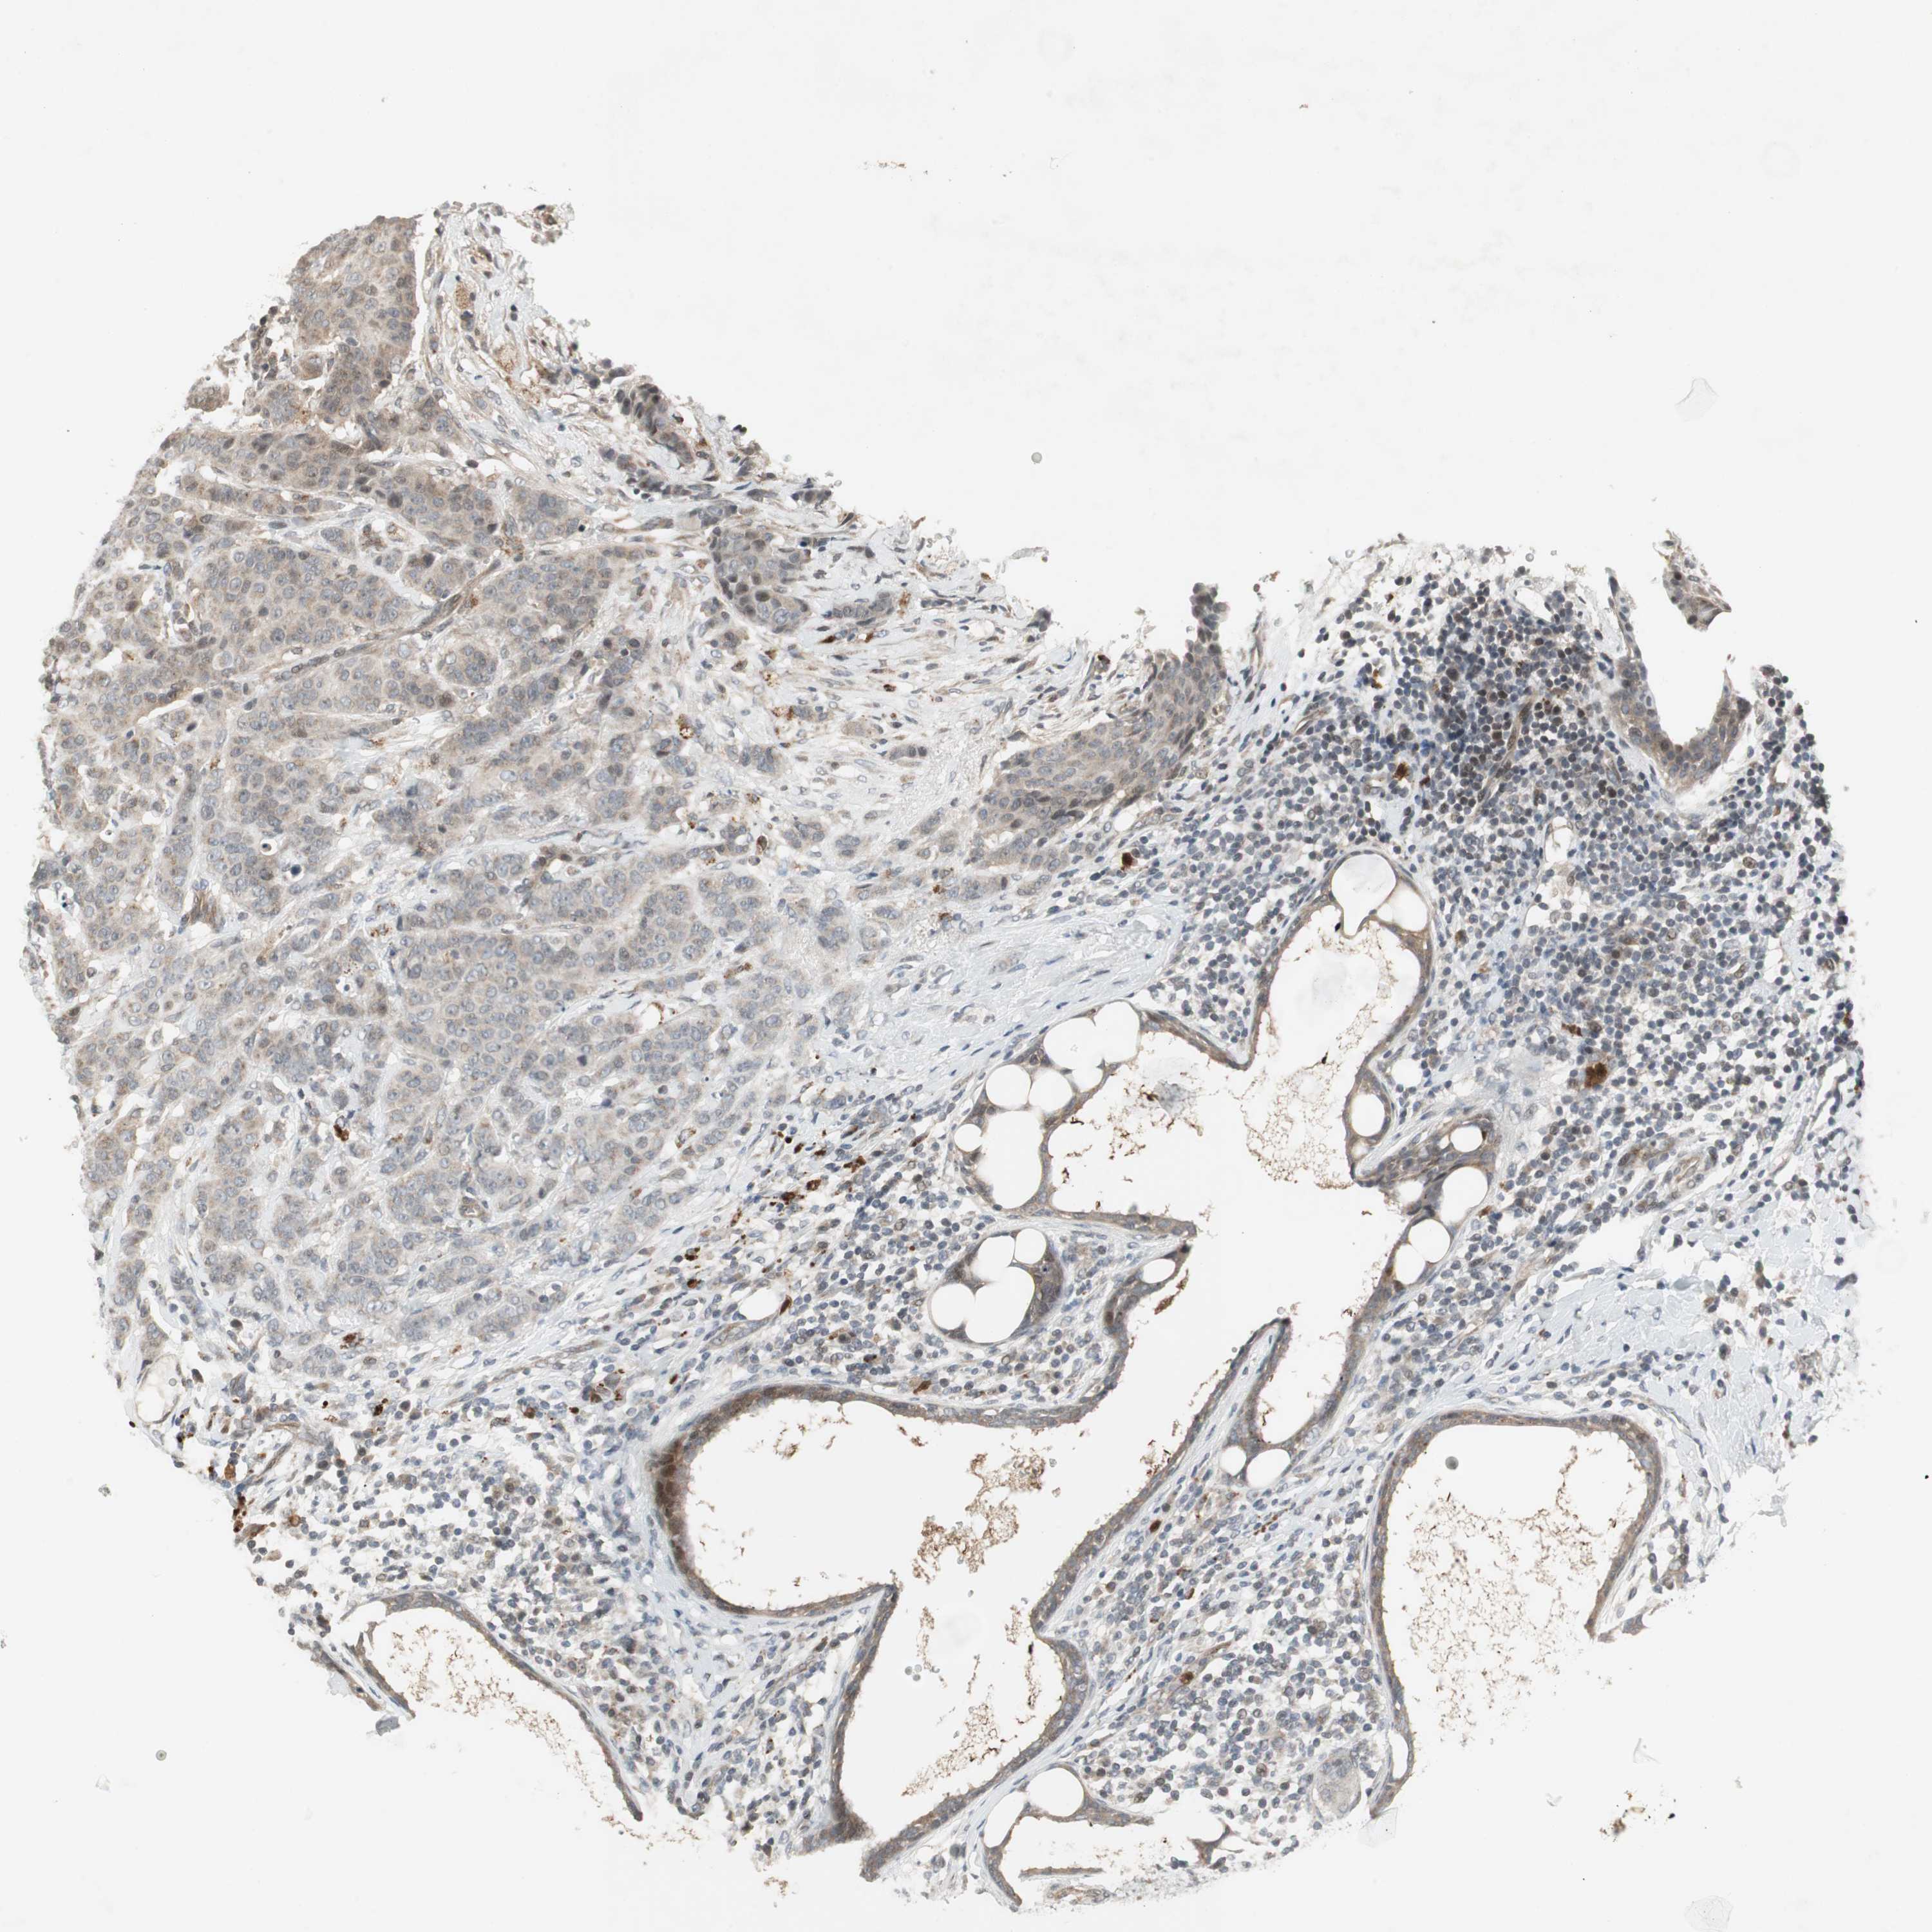

CANCER BREAST CANCER Show tissue menu

BRCA TCGA BRCA VALIDATION PROTEIN EXPRESSION